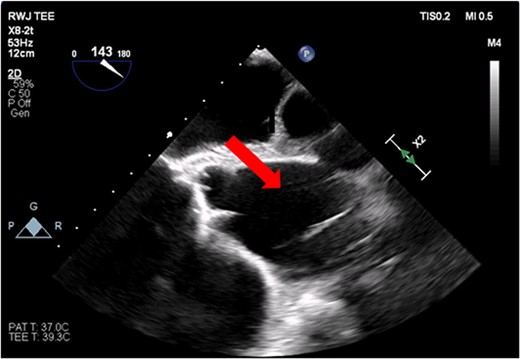

The patient’s milrinone dose was unable to be increased due to his risk for VT and his marginal blood pressures. A 50 cc 8 French left axillary IABP with proximal and distal markers was placed under fluoroscopy and transesophageal echo (TEE) guidance to prevent worsening of end-organ dysfunction and cardiogenic shock. About 3.5 weeks later, the patient received a heart transplant. His 20 gauge right radial arterial catheter was used for monitoring. There were no identifiable changes in the arterial line and the pressure waveforms. The patient was ambulatory in the intensive care unit (ICU) and showed no signs of decreased perfusion. After induction of general anesthesia, TEE showed the IABP in his aortic arch and ascending aorta with its tip placed proximally in the descending aorta (Figs 1 and 2).

Transesophageal image of the aortic root and ascending aorta with IABP present.